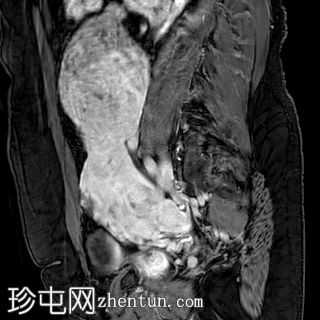

6个月前MRI检查

MRI

轴位

T2加权像

3.jpg

矢状位T1加权像

增强脂肪抑制像

4.jpg

与既往CT同时进行的MRI检查显示子宫内有多发性T2低信号强度肌瘤,但在子宫右侧一个肌瘤内可见一处不均匀、中心高T2/囊性信号区。

增强扫描图像显示,与其他肌瘤相比,该病灶呈异质性强化,强化区域混杂,中心大片区域无强化(与T2加权像上的囊性区域相对应)。